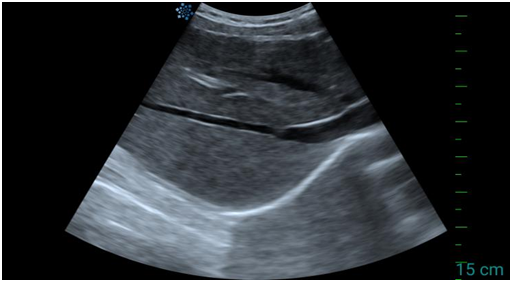

二、肝脏超声“看”什么?

肝脏超声主要从以下几个方面评估你的肝脏健康:

2. 肝脏的“内在质地”

肝实质回声:正常肝脏的回声是均匀细腻的。如果回声增强、增粗或不均匀,则提示可能存在病变。